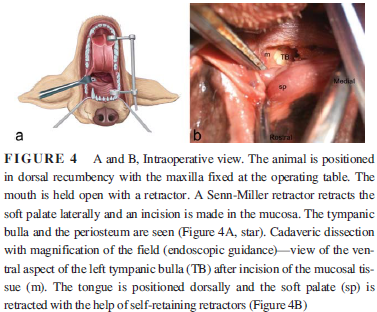

In an

August 2017 article, a team of French veterinary surgeons experimented with cadaver dogs to determine if

accessing the tympanic bulla through the mouth would be a practical

approach to installing a tympanostomy tube (TT) to allow for drainage

preventing recurring PSOM in cavalier King Charles spaniels. (See

the study's Figure 4 at right.) None of the

dogs were CKCSs in this study. They found that, in all cases, the

tympanic bulla osteotomy was performed without requiring access through

the ear canal and without damaging the inner ear or any neurovascular

structures. They noted that this oral approach to the tympanic bulla was

easier in mesaticephalic and dolichocephalic dogs than in brachycephalic

breeds. They concluded that, in spite of its small diameter, TT provides

constant ventilation and drainage of the middle ear cavity, resulting in

improved hearing and quality of life. They went on:

In an

August 2017 article, a team of French veterinary surgeons experimented with cadaver dogs to determine if

accessing the tympanic bulla through the mouth would be a practical

approach to installing a tympanostomy tube (TT) to allow for drainage

preventing recurring PSOM in cavalier King Charles spaniels. (See

the study's Figure 4 at right.) None of the

dogs were CKCSs in this study. They found that, in all cases, the

tympanic bulla osteotomy was performed without requiring access through

the ear canal and without damaging the inner ear or any neurovascular

structures. They noted that this oral approach to the tympanic bulla was

easier in mesaticephalic and dolichocephalic dogs than in brachycephalic

breeds. They concluded that, in spite of its small diameter, TT provides

constant ventilation and drainage of the middle ear cavity, resulting in

improved hearing and quality of life. They went on:

"We speculate that the transoral approach of the tympanic bulla could be used in cases of refractory PSOM treated with TT, or in cases where repeated TT placement and associated anesthetic episodes, are contraindicated due to the general condition of the patient. Removal of the entire ventral portion of the TB creates a larger opening than the TT and should therefore result in superior drainage."

August 2017:

French surgeons test an oral approach to installing tympanostomy

tubes in cavaliers with PSOM.

In an

August 2017 article, a team of French veterinary surgeons (Maria

Manou, Pierre H. M. Moissonnier, Nicolas Jardel, Aymeric Tissier,

Rosario Vallefuoco) experimented with cadaver dogs to determine if

accessing the tympanic bulla through the mouth would be a practical

approach to installing a tympanostomy tube (TT) to allow for drainage

preventing recurring PSOM in cavalier King Charles spaniels. (See

the study's Figure 4 at right.) None of the

dogs were CKCSs in this study. They found that, in all cases, the

tympanic bulla osteotomy was performed without requiring access through

the ear canal and without damaging the inner ear or any neurovascular

structures. They noted that this oral approach to the tympanic bulla was

easier in mesaticephalic and dolichocephalic dogs than in brachycephalic

breeds. They concluded that, in spite of its small diameter, TT provides

constant ventilation and drainage of the middle ear cavity, resulting in

improved hearing and quality of life. They went on:

In an

August 2017 article, a team of French veterinary surgeons (Maria

Manou, Pierre H. M. Moissonnier, Nicolas Jardel, Aymeric Tissier,

Rosario Vallefuoco) experimented with cadaver dogs to determine if

accessing the tympanic bulla through the mouth would be a practical

approach to installing a tympanostomy tube (TT) to allow for drainage

preventing recurring PSOM in cavalier King Charles spaniels. (See

the study's Figure 4 at right.) None of the

dogs were CKCSs in this study. They found that, in all cases, the

tympanic bulla osteotomy was performed without requiring access through

the ear canal and without damaging the inner ear or any neurovascular

structures. They noted that this oral approach to the tympanic bulla was

easier in mesaticephalic and dolichocephalic dogs than in brachycephalic

breeds. They concluded that, in spite of its small diameter, TT provides

constant ventilation and drainage of the middle ear cavity, resulting in

improved hearing and quality of life. They went on:

"We speculate that the transoral approach of the tympanic bulla could be used in cases of refractory PSOM treated with TT, or in cases where repeated TT placement and associated anesthetic episodes, are contraindicated due to the general condition of the patient. Removal of the entire ventral portion of the TB creates a larger opening than the TT and should therefore result in superior drainage."